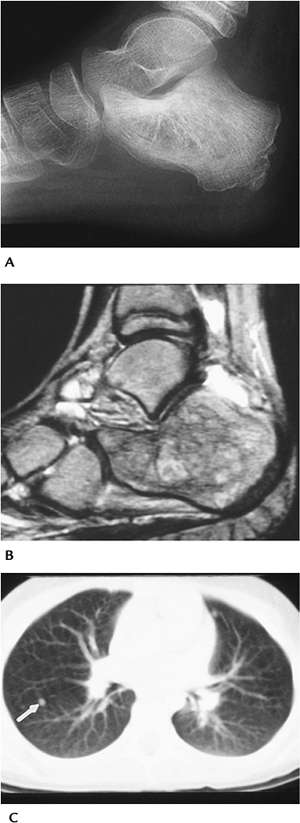

![]() |

FIGURE 6-68 Ewing sarcoma of calcaneus. (A) Routine lateral radiograph showing bone sclerosis. (B) Sagittal T2-weighted image showing irregular signal intensity with joint fluid. Ewing sarcoma of calcaneus. (A) Routine lateral radiograph showing bone sclerosis. (B) Sagittal T2-weighted image showing irregular signal intensity with joint fluid. (C) CT of chest showing a metastatic nodule (arrow).